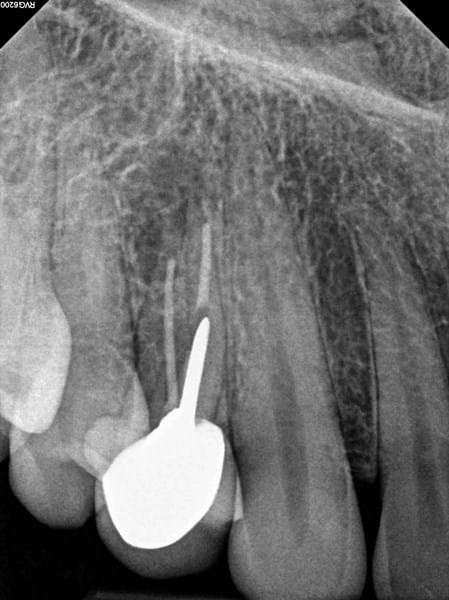

Extracción o re endodoncia, que es lo mejor? RX adjuntos

Les comento que hace algunos años, me hicieron una endodoncia en la pieza 14, que resulto con una quebradura de una de las puntas del diente, posteriormente se me reparó con una incrustación, la cual falló y finalmente otro dentista me realizó una corona dental. Hace 4 años aproximandamente, todos los años me realizo una limpieza dental y rapaje si es necesario.

En julio de este año, me apareciò un absceso sobre el diente (corona), que fue tratado con antibiotico (amoxicilina) y la infección se fue, pero luego de unos meses esta infección volvió consultè a un dentista que decide que hay que extraer la pieza dental y realizar un implante, posteriormente consulté otro dentista que recomienda, realizar el tratamiento conducto nuevamente y colocar corona nueva, o bien realizar un procedimiento desde afuera para re limpiar el canal, porque dice que el conducto esta bueno, y es una parte de nervio que quedó porque la endodoncia quedo mal hecha desde un principio.

Adjunto los rayos X